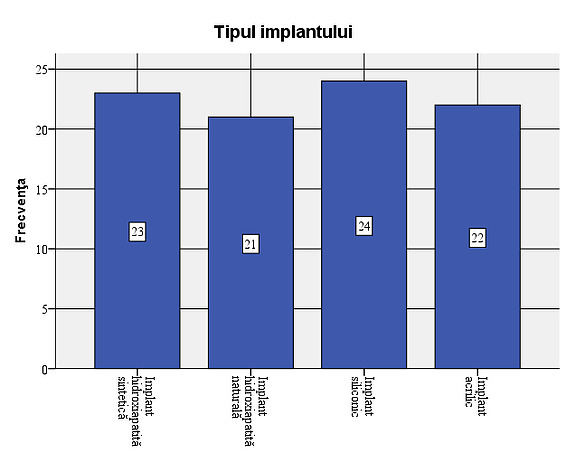

Figure 1: Gender distribution in the study. The presence of a larger number of male patients is due to the large number of eviscerations after ocular trauma, a pathology more frequently encountered in males (33 cases). The implant types were used in a relatively equal proportion: in 26.7% of patients the silicone implant was used, in 25.6% the synthetic hydroxyapatite implant, in 24.4% the acrylic implant, and in 23.3% the natural hydroxyapatite implant.

- The types of implant were used in a relatively equal proportion: in 26.7% of the patients the silicone implant was used, in 25.6% the synthetic hydroxyapatite implant (FCI3), for 24.4% the acrylic implant (PMMA), and for 23.3% the natural hydroxyapatite implant (Bio-Eye);